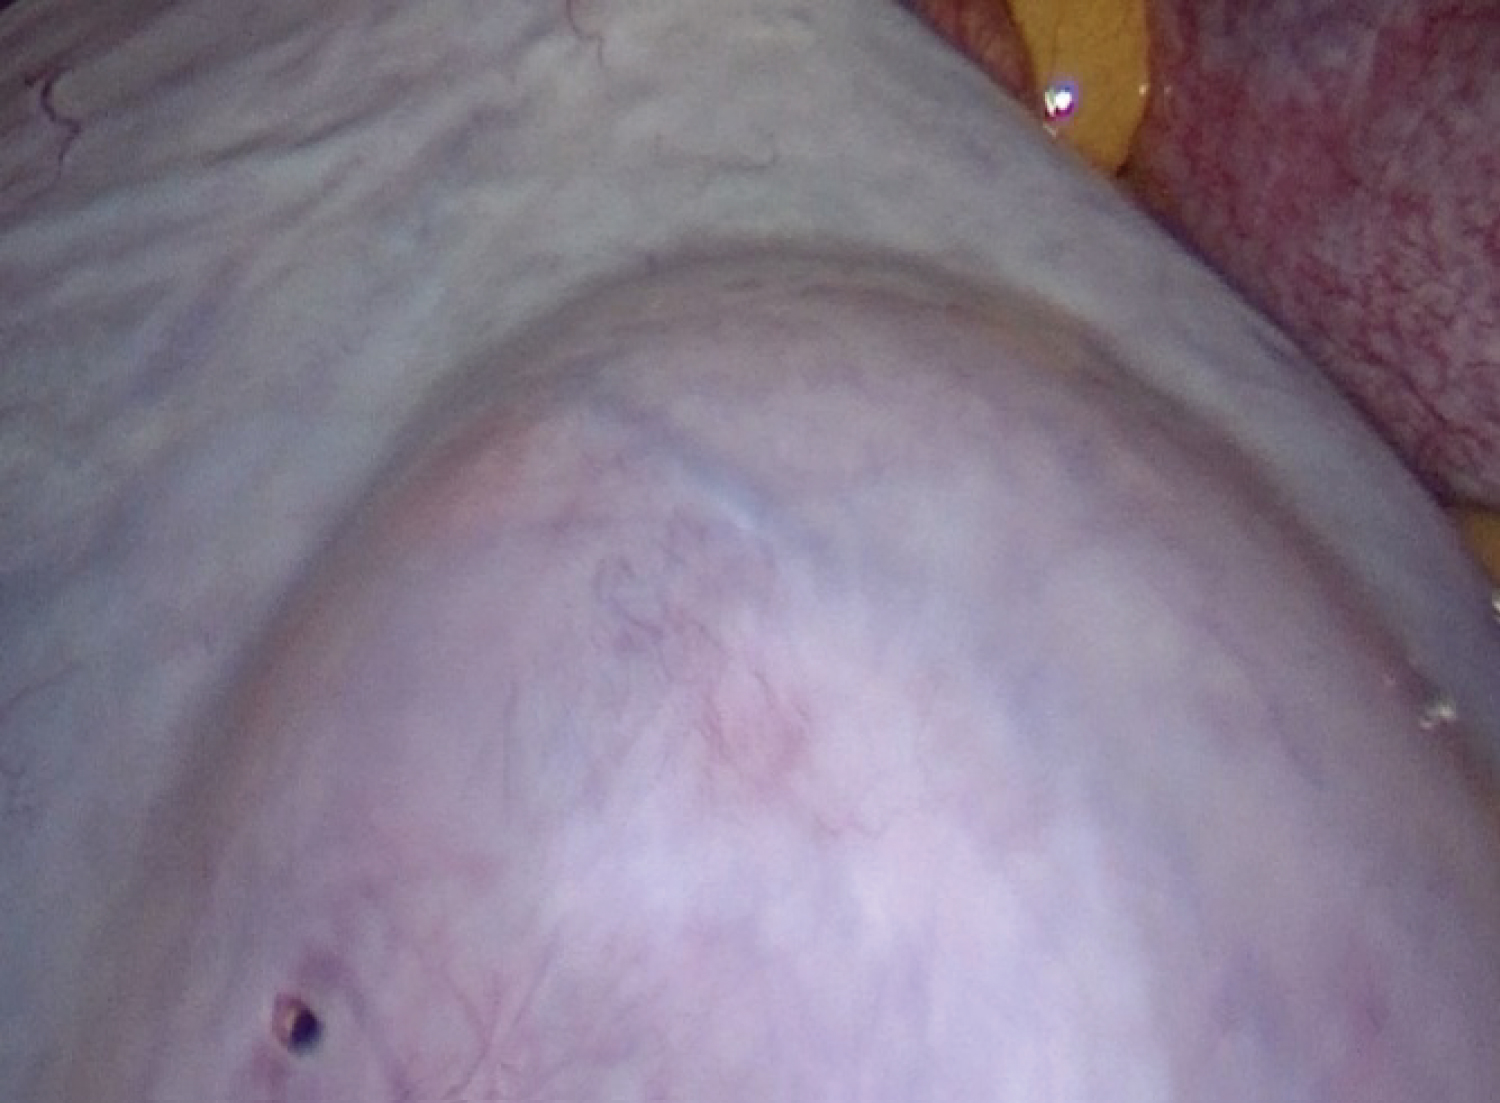

When we were faced with a patient who was in severe pain, we decided to perform a diagnostic laparoscopy. Exploration revealed a large functional cyst measuring 15 * 10 cm (Figure 1). The fallopian tube was twisted with three turns of the spiral (Figure 2) and an epiploic appendigitis (Figure 3). After evacuation of the cyst, a detorsion was performed. Yellow fluid was obtained, confirming the functional origin of the cyst, followed by resection of the epiploic appendigitis. Postoperative follow-up was favorable and the patient was discharged one day later. The ultrasound after 2 weeks showed an evolving pregnancy.

Figure 1: Ovarian cyst. View Figure 1